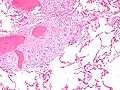

Sarcoidosis in a lymph node